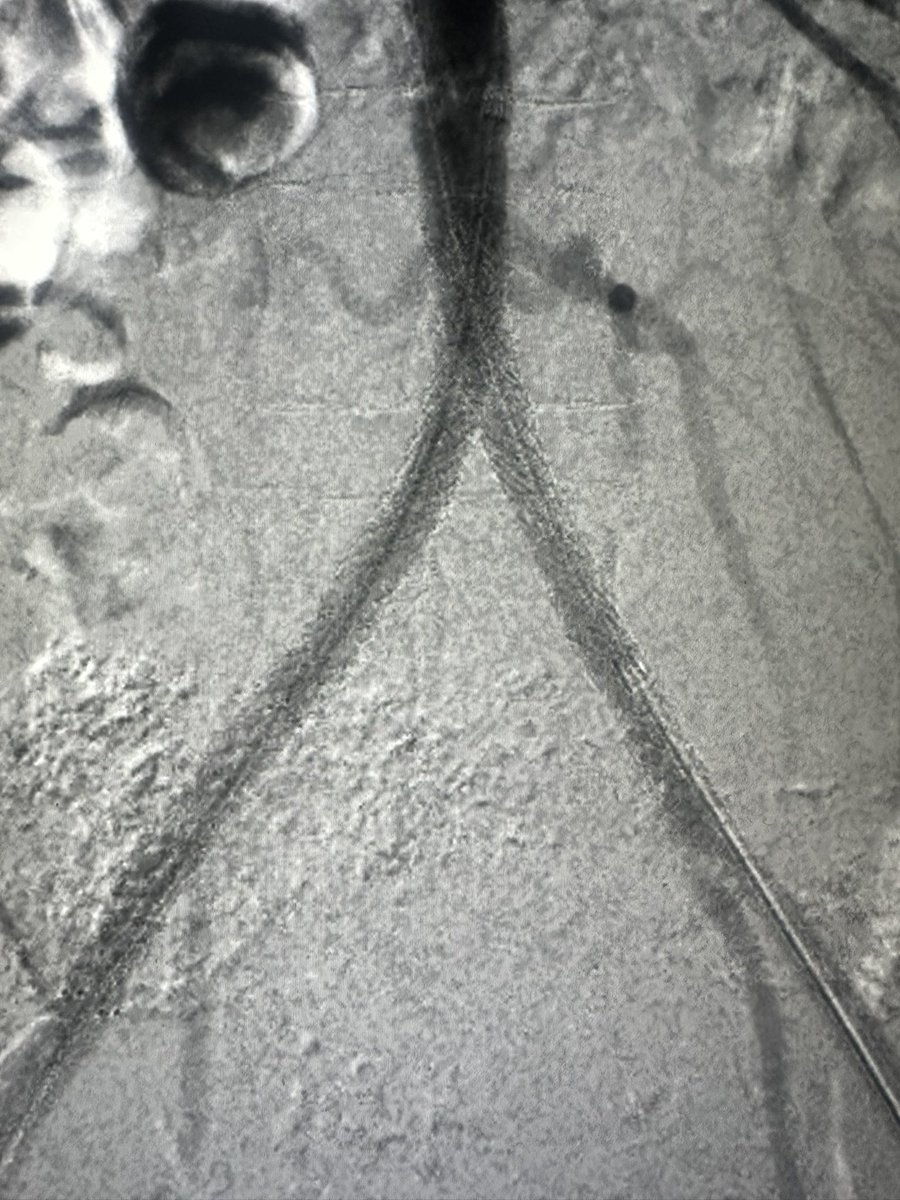

Catheter-related intimal tear/focal dissection at proximal LAD in a 50 year old male, during this pre-AVR elective diagnostic cath. Angio + #IVUS below 👇 ♦️How would you manage? 🤨 #ACCFIT #CardioTwitter #Cardiology @SCAI @ACCinTouch #RadialFirst @BCMHeart @AkuCardiology